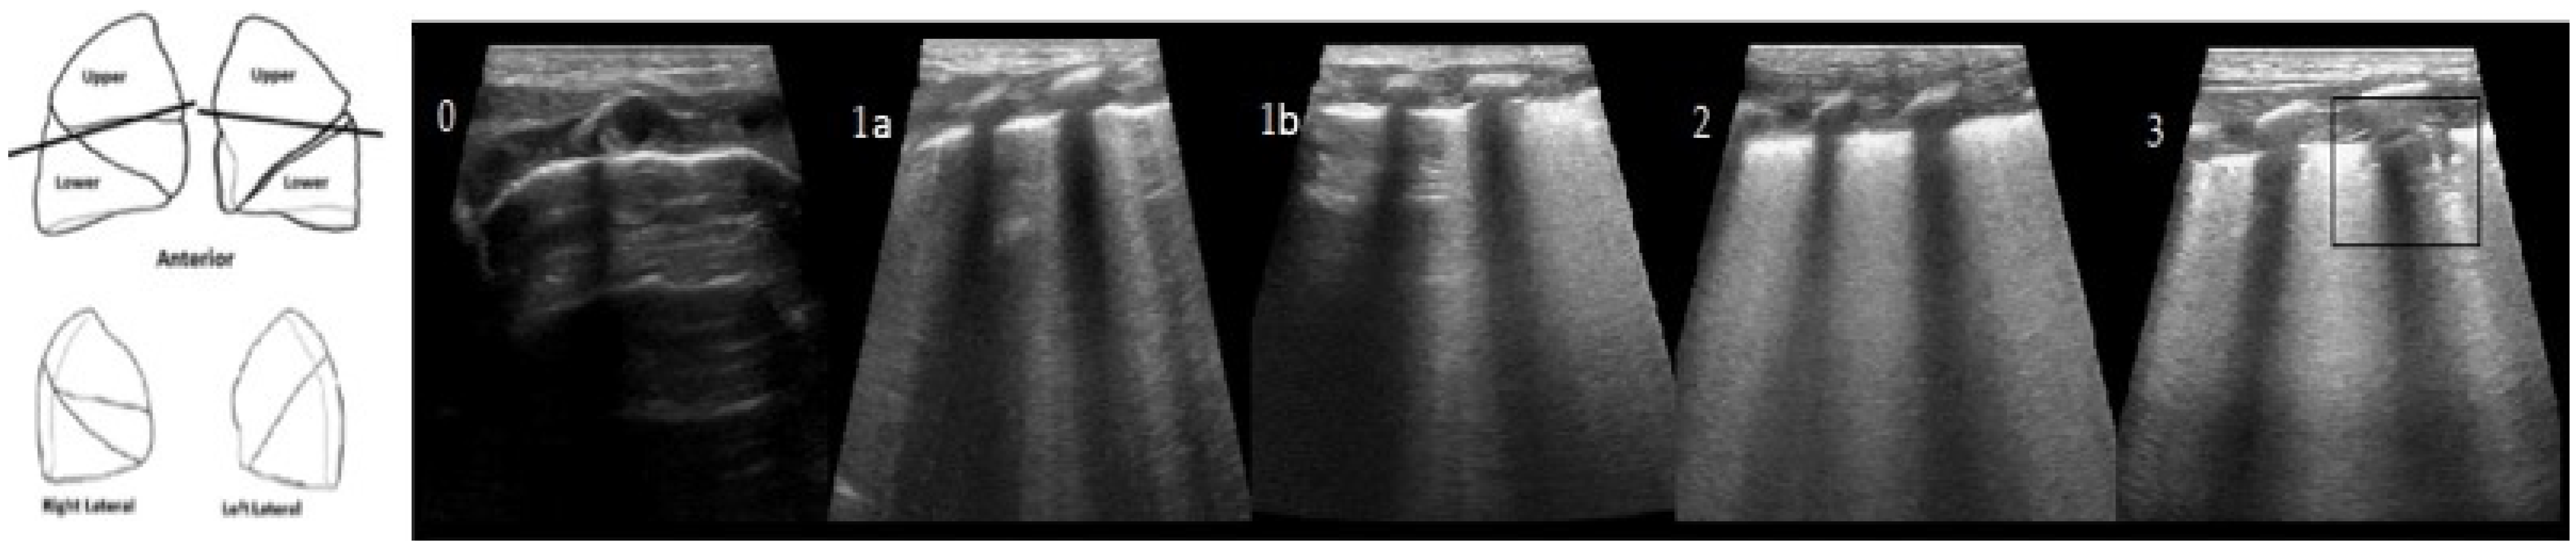

3. Results